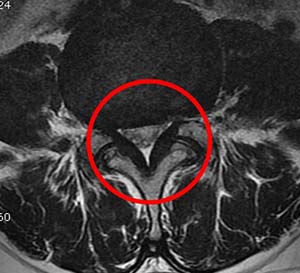

오늘 글에서는 척추관 협착증 증상 치료방법에 대해서 알아보도록 하겠어요. 척추관 협착증은 퇴행성 디스크와 아울러 전형적인 퇴행성 척추질환입니다. 척추의 퇴행이 오래 진행되어 인대가 두꺼워지고 붓게 된다면 신경구멍이 좁아지며 척추관 협착증이 유발되요.

척추 관절과 인대가 변경되고 두꺼워져 척추 신경을 조이면 신경의 혈액순환이 모자라게 되어 생겨해요. 선천적으로 요추관의 정도가 정상보다 작게 만들어지는 경우로, 대개는 35세가 넘어 뼈와 인대의 변환가 연거푸해서 증상이 형성되나 20세 전후의 아주 젊은 나이에도 띄엄띄엄 발견되요.

최고 많이 보이는 원인으로 척추 퇴행성 골관절염이 생김에 따라 허리 관절의 정도가 많아지고 인대도 두꺼워지는 더불어 가시 같은 뼈가 자라나 신경 길을 좁아지게 해요.

척추관 협착증은 척추 관절과 주변 조직의 변화로 인해 나타나는 질환입니다. 이 질환의 원인은 자연적인 단계인 노화로 인한 척추 관절 연골 파괴와 뼈 형태적 전환, 디스크의 노화나 손상, 척추 골절, 척추 관절 염증, 그리고 선천적인 이상 등 각가지 요소들이 복합적으로 활동하여 생겨날수 있고요.

이러한 요소들은 척추관의 좁아짐과 신경 구조에 압력이 가해짐으로써 척추관 협착증을 일으킬 수 있습니다. 개인의 생활 습관, 유전적 요인, 부상 등도 사유로 작용할 수 있으며 각 개인의 경우에는 이러한 요소들이 복합적으로 작용하여 질환을 촉발합니다.